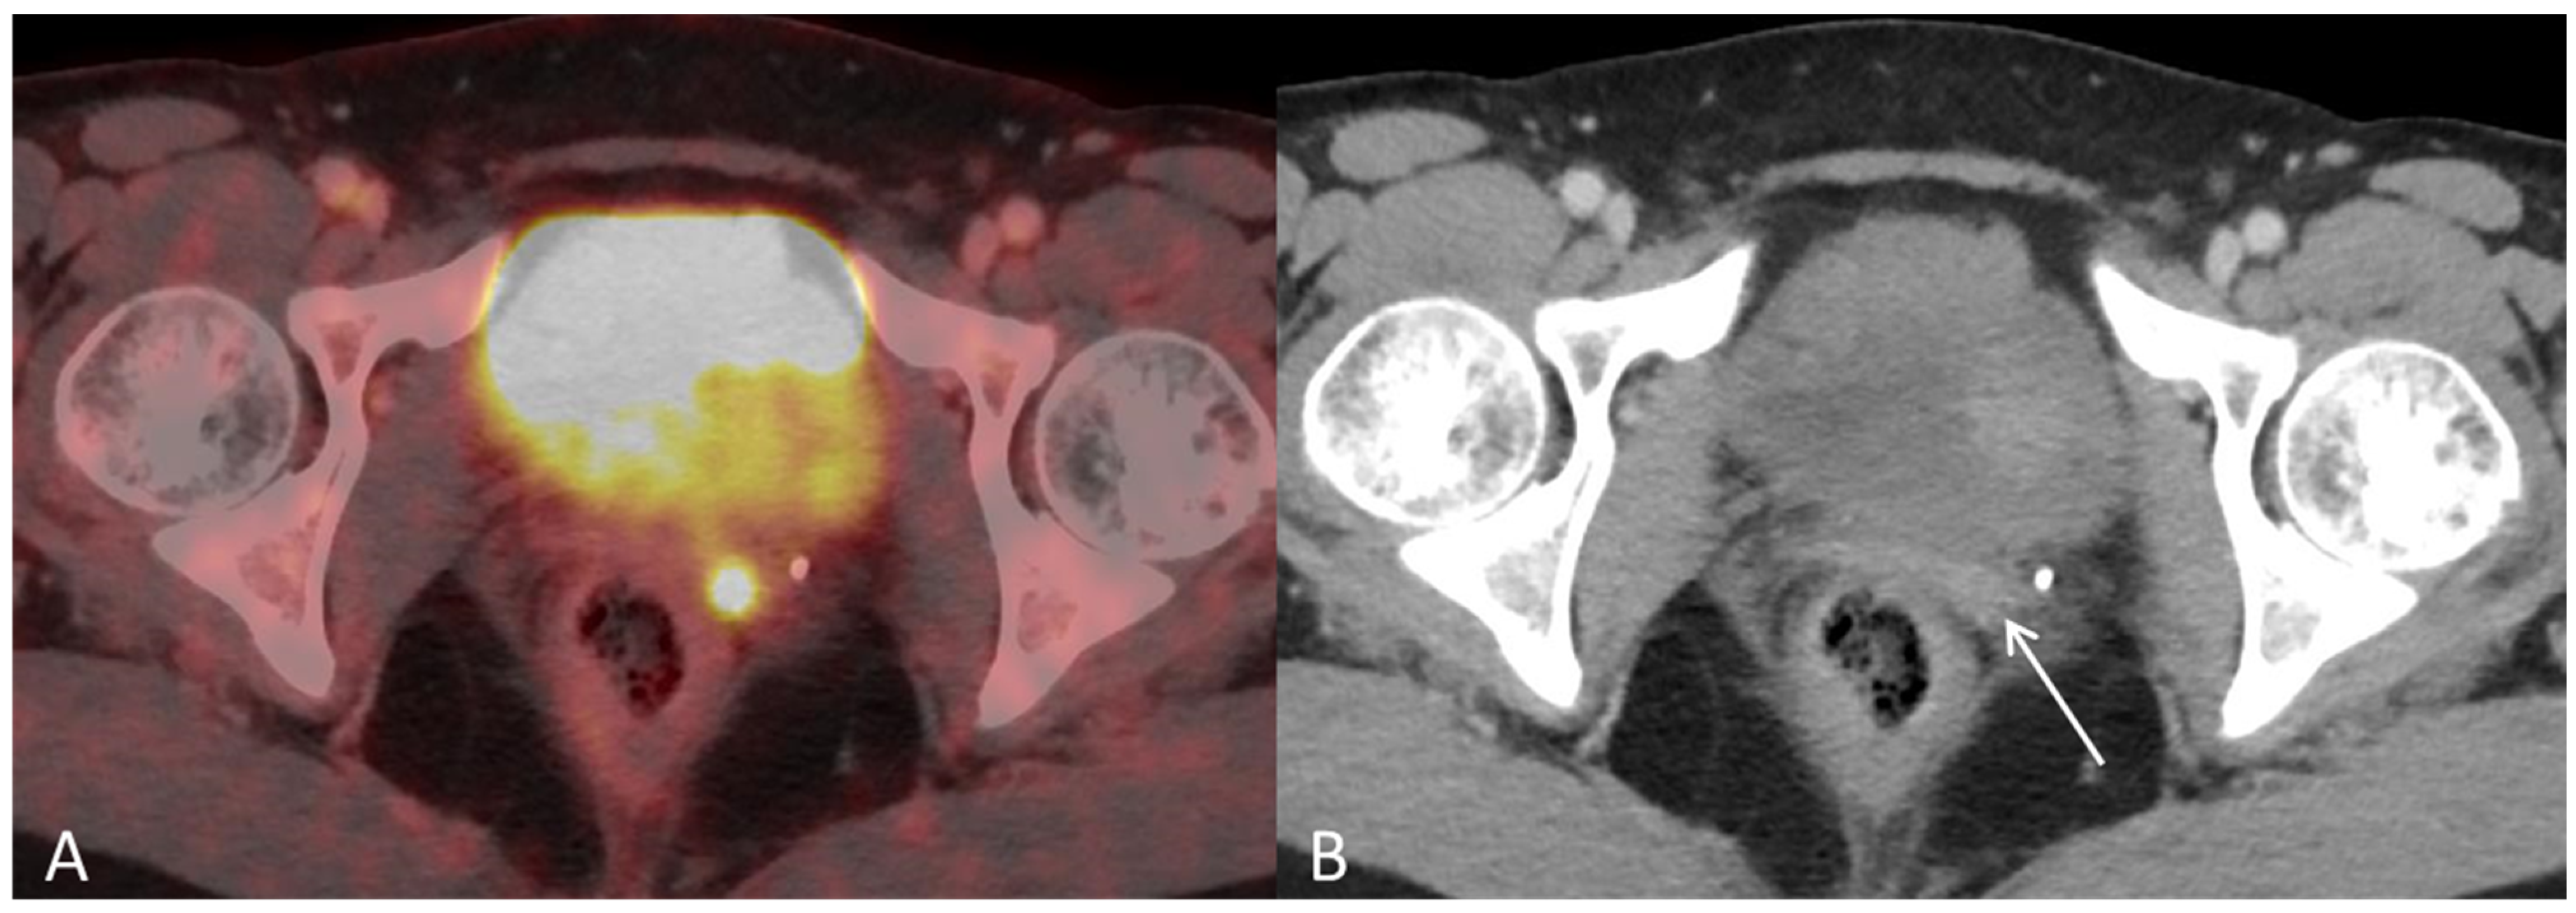

Disseminated Primary Uterine Hepatoid Adenocarcinoma with α-Fetoprotein Production Demonstrated on 18F-FDG PET/CT

Dejanovic, D.; Boennelycke, M.; Amtoft, A.G.; Christensen, C.B.; Wetterstroem, V.; Loft, A.; Noettrup, T.J. Disseminated Primary Uterine Hepatoid Adenocarcinoma with α-Fetoprotein Production Demonstrated on 18F-FDG PET/CT. Diagnostics 2022, 12, 1447. https://doi.org/10.3390/diagnostics12061447